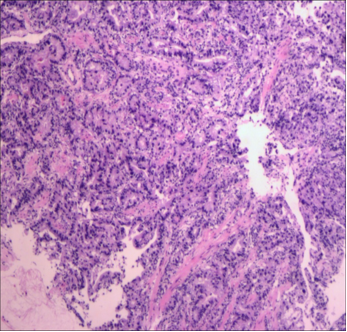

术后病理检查显示,胃壁内可见钙化、纤维化及炎细胞浸润,符合治疗后改变,上、下切缘:(-);大网膜:(-);淋巴结:LN:0/25 ypT0N0M0 TRG 0级(图3)。

20.3.png图3. 术后病理检查